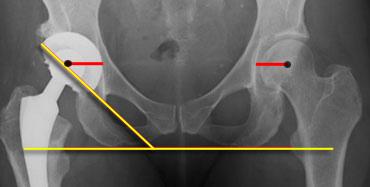

Measurement of lateral acetabular inclination. Right trochanter minor is lower in position than the left indicating leg length dicrepancy.Normal horizontal center of rotation (red line).

Alignment and Positioning

Vị trí đặt cốc acetabulum và thân xương đùi cần mô phỏng giải phẫu bình thường.

Khoảng cách từ tâm chỏm xương đùi đến điểm lệ (hoặc mốc giải phẫu có thể xác định khác) phải bằng nhau ở cả hai bên.

Đây được gọi là tâm xoay ngang.

Vị trí đặt cốc acetabulum quá lệch ngoài làm tăng nguy cơ trật khớp và có thể gây đi khập khiễng.

Đường liên ụ ngồi được sử dụng làm mốc tham chiếu để đo độ nghiêng bên của cốc acetabular (30-50°).

Đường này cũng được sử dụng để đo sự chênh lệch chiều dài chân.

Chênh lệch chiều dài chân đến 1 cm được dung nạp tốt.

Cốc được đặt cao hơn được dung nạp tốt hơn so với cốc được đặt lệch ngoài.